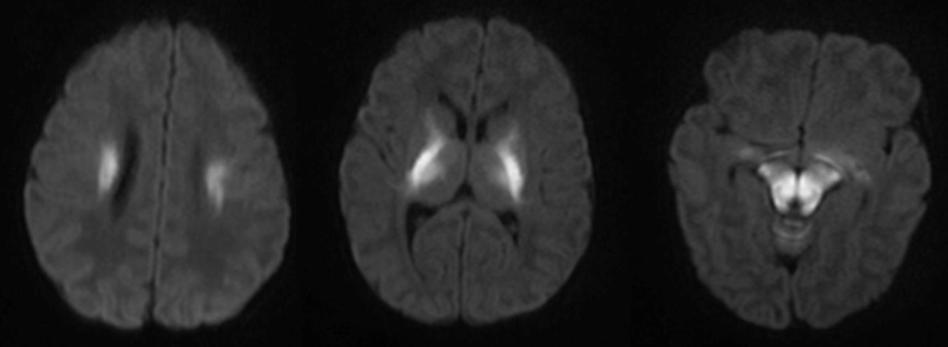

答案:Susac综合征。Susac综合征又称为视网膜耳蜗脑血管病变,是一种罕见的脑血管病,即不明原因的累及大脑、视网膜小动脉和耳蜗的微血管病变,导致典型的临床三联征:视网膜病、脑病、耳聋病,易误诊为多发性硬化和脑炎等。该病病程一般呈自限性,目前尚无有效的治疗方法。

本病首选MRI进行检查。

1)可见多发灰、白质小病灶,直径多为3-7mm,呈T1低信号、T2高信号影,主要位于胼胝体、侧脑室旁,42%的患者有幕上灰质病灶包括皮质与深部灰质,43%的患者有幕下病灶,包括脑干与小脑,约50%的患者可出现病灶强化,23%的患者伴有软脑膜强化。

2)胼胝体受累以中央纤维为主,周围纤维则较少累及。胼胝体中央部微梗死灶急性期在FLAIR像中为高信号影,常表现为雪球样,也可表现为锥状或条索状。随着疾病的演变,梗死灶液化坏死,T1像表现为胼胝体中央部的“空洞征”,这是Susac综合征较为特异性的影像学表现。DWI可见内囊串珠样高信号影,系内囊微梗死灶引起,为Susac综合征的典型影像学特点。